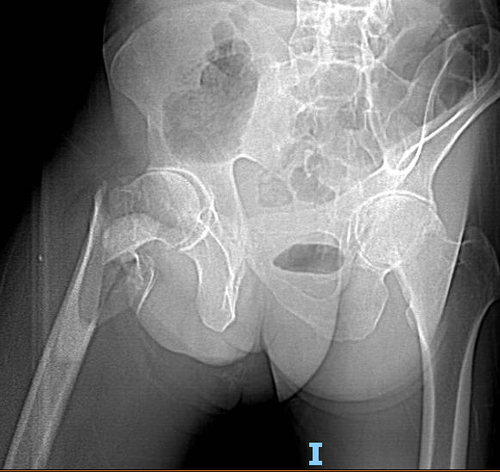

全功能智慧医院患者刘先生,数日前因不慎摔伤致全身多处外伤,以腰部及右髋部症状体征为著。于当地医院就诊,但因基础疾病较多,保守治疗多日后,患者出现失血性休克以及右下肢肌间静脉血栓形成症状,当地医院查血色素仅为39g/L,紧急输血后告知需转上级医院继续治疗。

患者女儿在济南工作,多名亲属曾就诊于济南市中心医院,均给予较高评价,为求进一步治疗,刘先生在家属及朋友陪同下于急诊科就诊。创伤中心医师迅速评估患者生命体征,并紧急查血示血色素60g/L,查体右下肢皮肤色素沉着,肿胀明显,压痛明显,肢体外旋外展畸形,腹股沟中点压痛阳性,右髋部活动不能。予以紧急备血输血并完善检查,请相关科室会诊并对症治疗后,收住创伤中心病房。

创伤中心孟祥海副主任医师查体后发现,患者骨质疏松,基础疾病较多。患肢转子间粉碎性骨折,骨折端不仅粉碎且股骨大小转子均发生明显移位,骨折线累及股骨转子下。综合患者一般情况,手术难度较大,且手术及麻醉风险较高,但患者于外院已出现卧床并发症表现,需要进一步调理,身体情况允许后再予以手术治疗,最大限度恢复患肢功能,争取早期下地活动,增强生活质量。